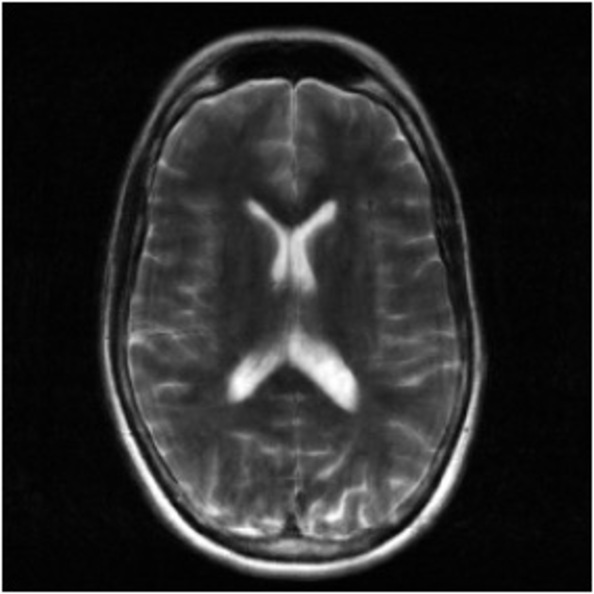

Figure 2: Example MRI magnitude reconstructions with S=25S=25 training slices at acceleration factor R=7R=7. PaDIS-MRI reconstructions are sharper and more faithful to the fully-sampled ground truth. Insets are shown to highlight detail.

Figure 2 provides a visual comparison of the reconstruction quality of each method on example slices. In reconstructions from the S=25,R=7S=25,R=7 models, FastMRI-EDM exhibits slightly more blurring and loss of fine structural details, particularly in regions with complex anatomical features. PaDIS-MRI, in contrast, preserves sharper boundaries and finer details. This enhanced data efficiency can be attributed to the patch-based prior’s ability to learn localized structural motifs more effectively from limited examples. Figure 6 in the Appendix shows similar reconstructions at S=200,R=7S=200,R=7 where FastMRI-EDM more closely approaches the performance of PaDIS-MRI but still struggles with highly detailed anatomy. At both dataset sizes, MoDL underperforms the diffusion priors. In Figure 2, MoDL’s FLAIR reconstruction exhibits pronounced artifacts, likely reflecting reduced generalizability of a supervised prior when the training distribution underrepresents FLAIR.